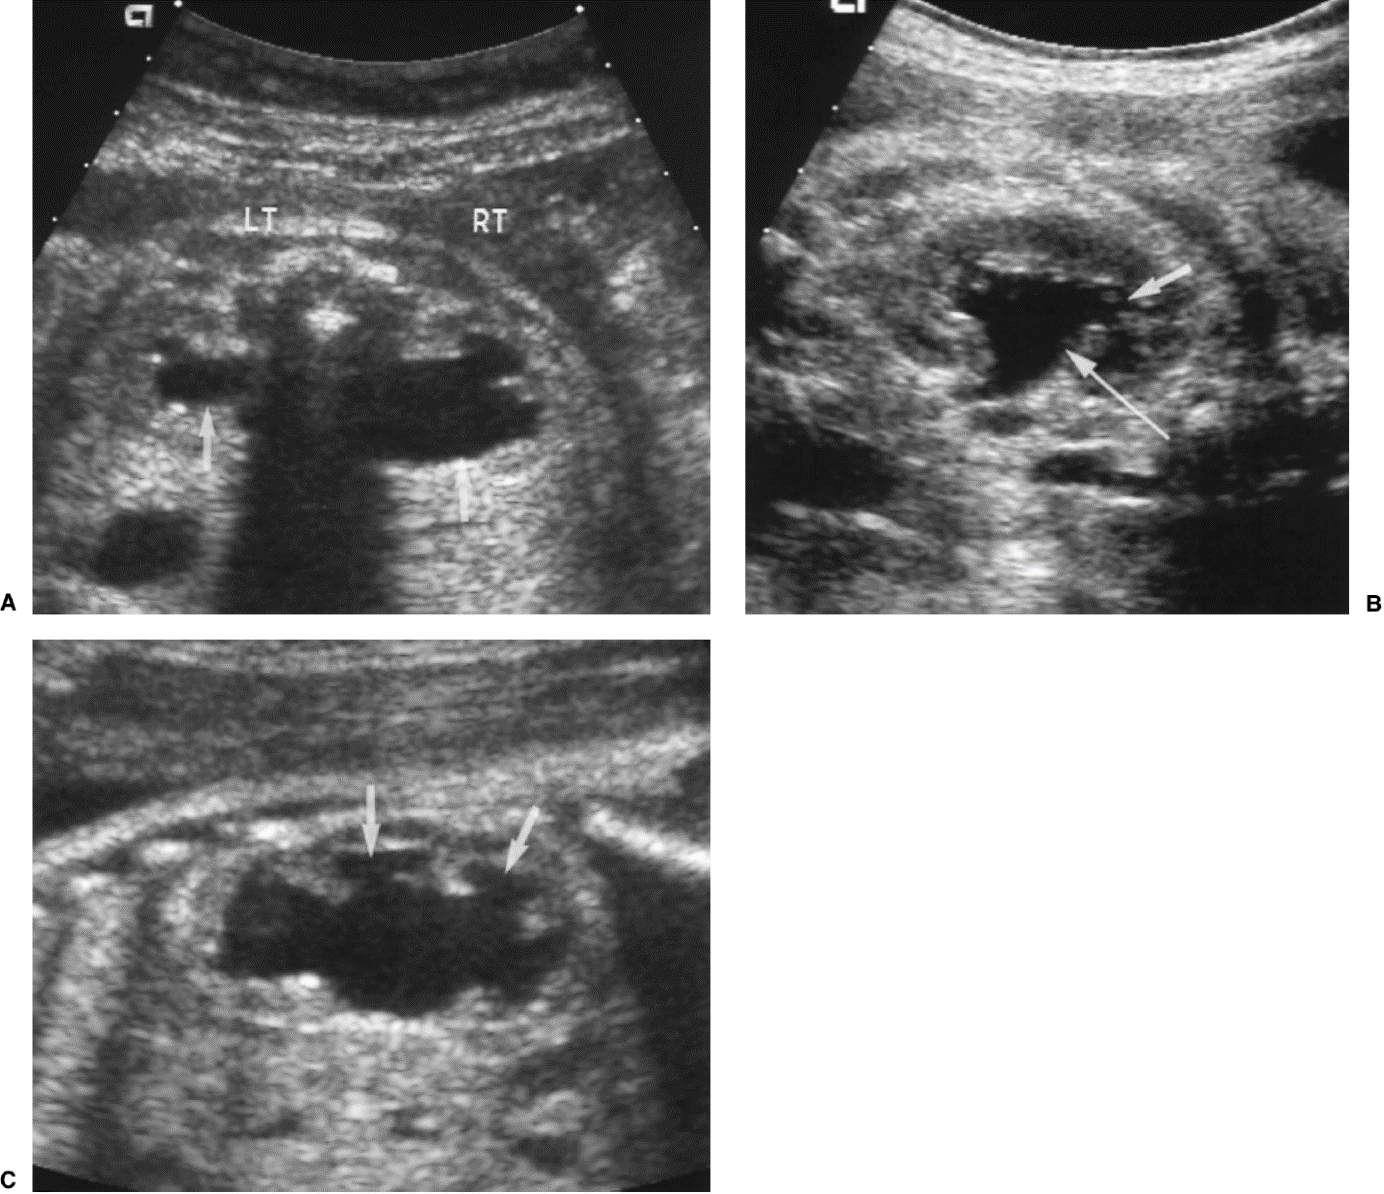

20 weken echografie: links: dikwandige blaas met verwijding van de plasbuis tot aan de kleppen (pijl): het “sleutelgat teken”. Onder: verwijde urineleiders. Bij kinderen gaan de urineleiders bij verwijding ook erg gekronkeld verlopen.